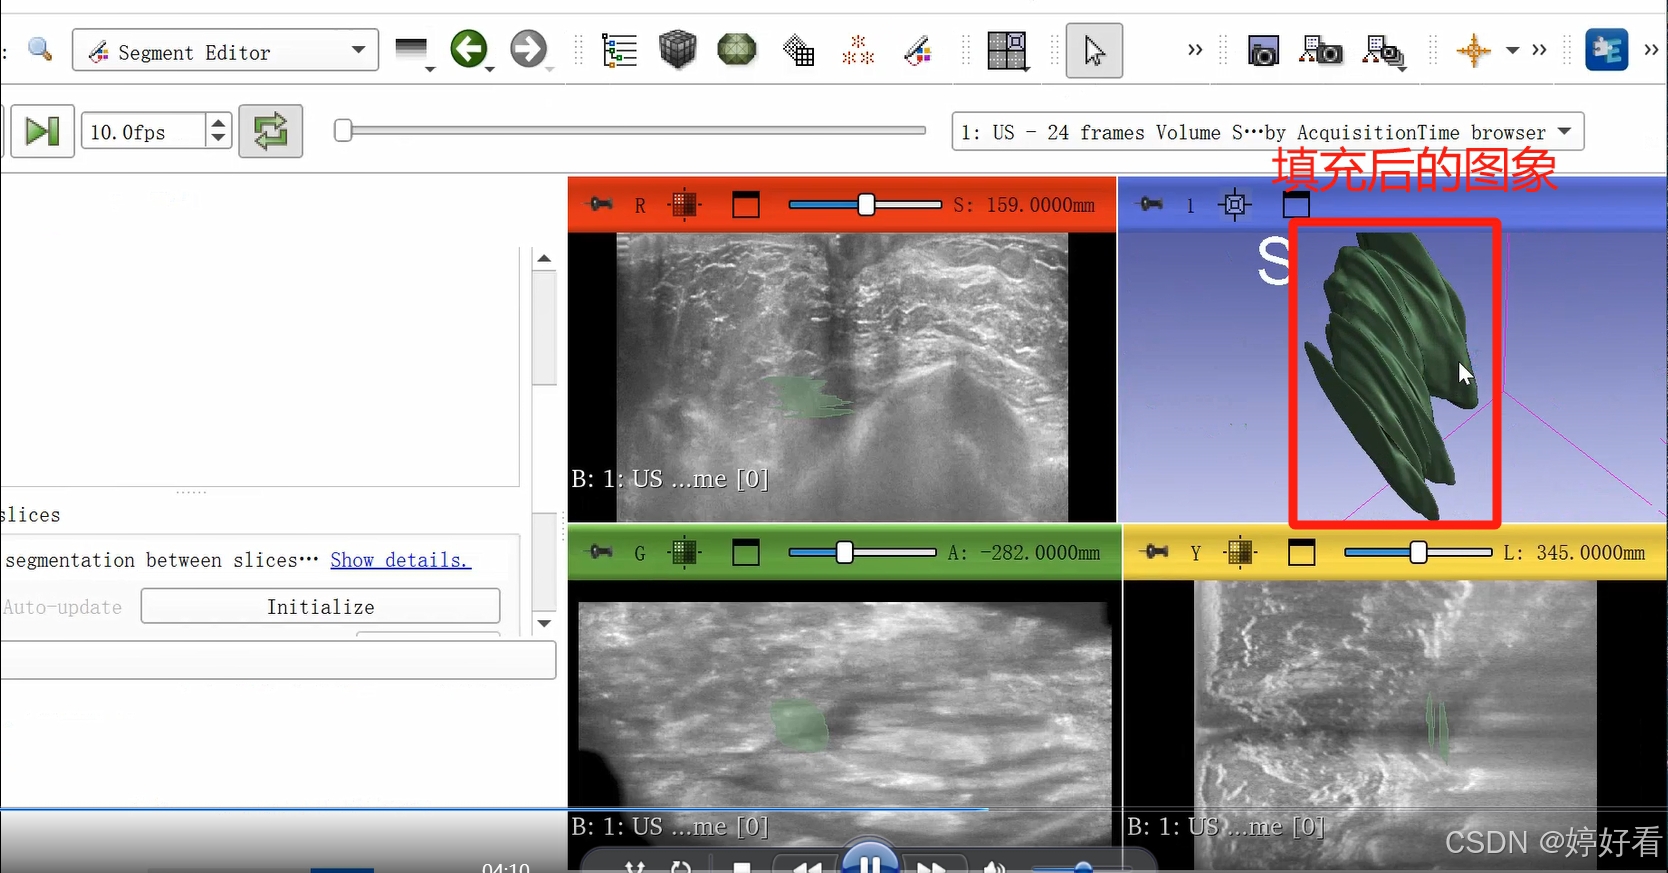

2.6 使用Fill between slices功能

上一步中完成的三维图像不是完整连续的三维图像,是一层一层的。Fill between slices这个功能可以自动填充每一层之间的间隙。选中Fill between slices,然后依次点击Initialize-Apply。